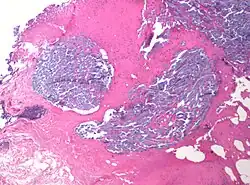

Desmoplasia refers to growth of dense connective tissue or stroma.[2] This growth is characterized by low cellularity with hyalinized or sclerotic stroma and disorganized blood vessel infiltration.[3] This growth is called a desmoplastic response and occurs as result of injury or neoplasia.[2] This response is coupled with malignancy in non-cutaneous neoplasias, and with benign or malignant tumors if associated with cutaneous pathologies.[3]

Characteristics of desmoplastic stromal response

A desmoplastic response is characterized by larger stromal cells with increased extracellular fibers and immunohistochemically by transformation of fibroblastic-type cells to a myofibroblastic phenotype.[2] Myofibroblastic cells in tumors are differentiated from fibroblasts for their positive staining of smooth-muscle actin (SMA).[2] Furthermore, an increase in total fibrillar collagens, fibronectins, proteoglycans, and tenascin C are distinctive of the desmoplastic stromal response in several forms of cancer.[14] Expression of tenascin C by breast cancer cells has been demonstrated to allow for metastasis to the lungs and cause the expression of tenascin C by the surrounding tumor stromal cells.[15] In addition, tenascin C is found extensively in pancreatic tumor desmoplasia as well.[16]